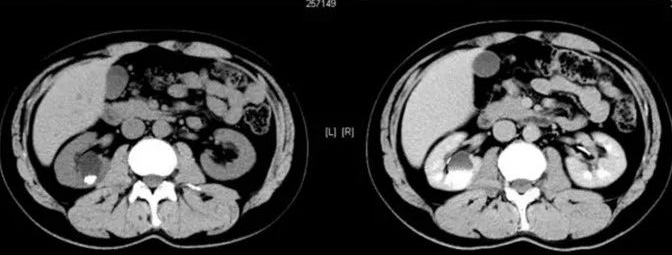

患者男性 43 岁 因左侧腰背部疼痛不适,左侧腰背部叩击疼阳性,门诊拟:「 肾结石 」 行 CT 检查;

咦!没有发现明显的阳性结石啊,就左肾囊肿;

我们建议 CT 增强扫描;

动脉期

静脉期

这不就是囊肿嘛?还有什么疑问?

笔者:你跟患者说,让他再起来到门口不要走开,等 15 分钟后再给回来扫一次,仰卧位扫一次,俯卧位扫一次;

15 分钟后,患者再次扫描

俯卧位

笔者:你看看发现什么不一样的嘛?

技师:咦!这个囊肿和以前的囊肿不一样啊,它怎么会发生强化呢?

笔者:这真的就是囊肿嘛?

2、肾盏憩室主要表现为:肾内囊性占位,平扫时囊性灶与肾盏分界不清,增强后造影剂进入囊肿(主要在延迟期造影剂进入憩室内);有时囊肿内可以看到结石或者钙乳样沉积物;肾盏憩室病灶主要偏向外周生长。